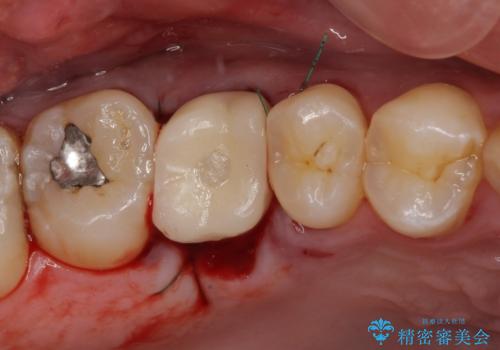

インプラント処置は、抜歯即時埋入を行い、十分な安定性が確認できたため、当日仮歯を装着しました。

インプラントが生着するのを待っている間に反対側の根管治療を行い、左右同時に補綴治療を行いました。

補綴治療後3ヶ月での経過は良好で、引き続き経過観察を行っていきます。